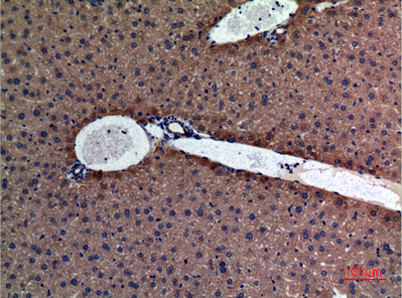

Product name: Amylase rabbit pAb

Dilutions: Western Blot: 1/500 - 1/2000. IHC-p: 1:100-300 ELISA: 1/20000. Not yet tested in other applications.

Immunogen: The antiserum was produced against synthesized peptide derived from the N-terminal region of human AMY1/2. AA range:61-110